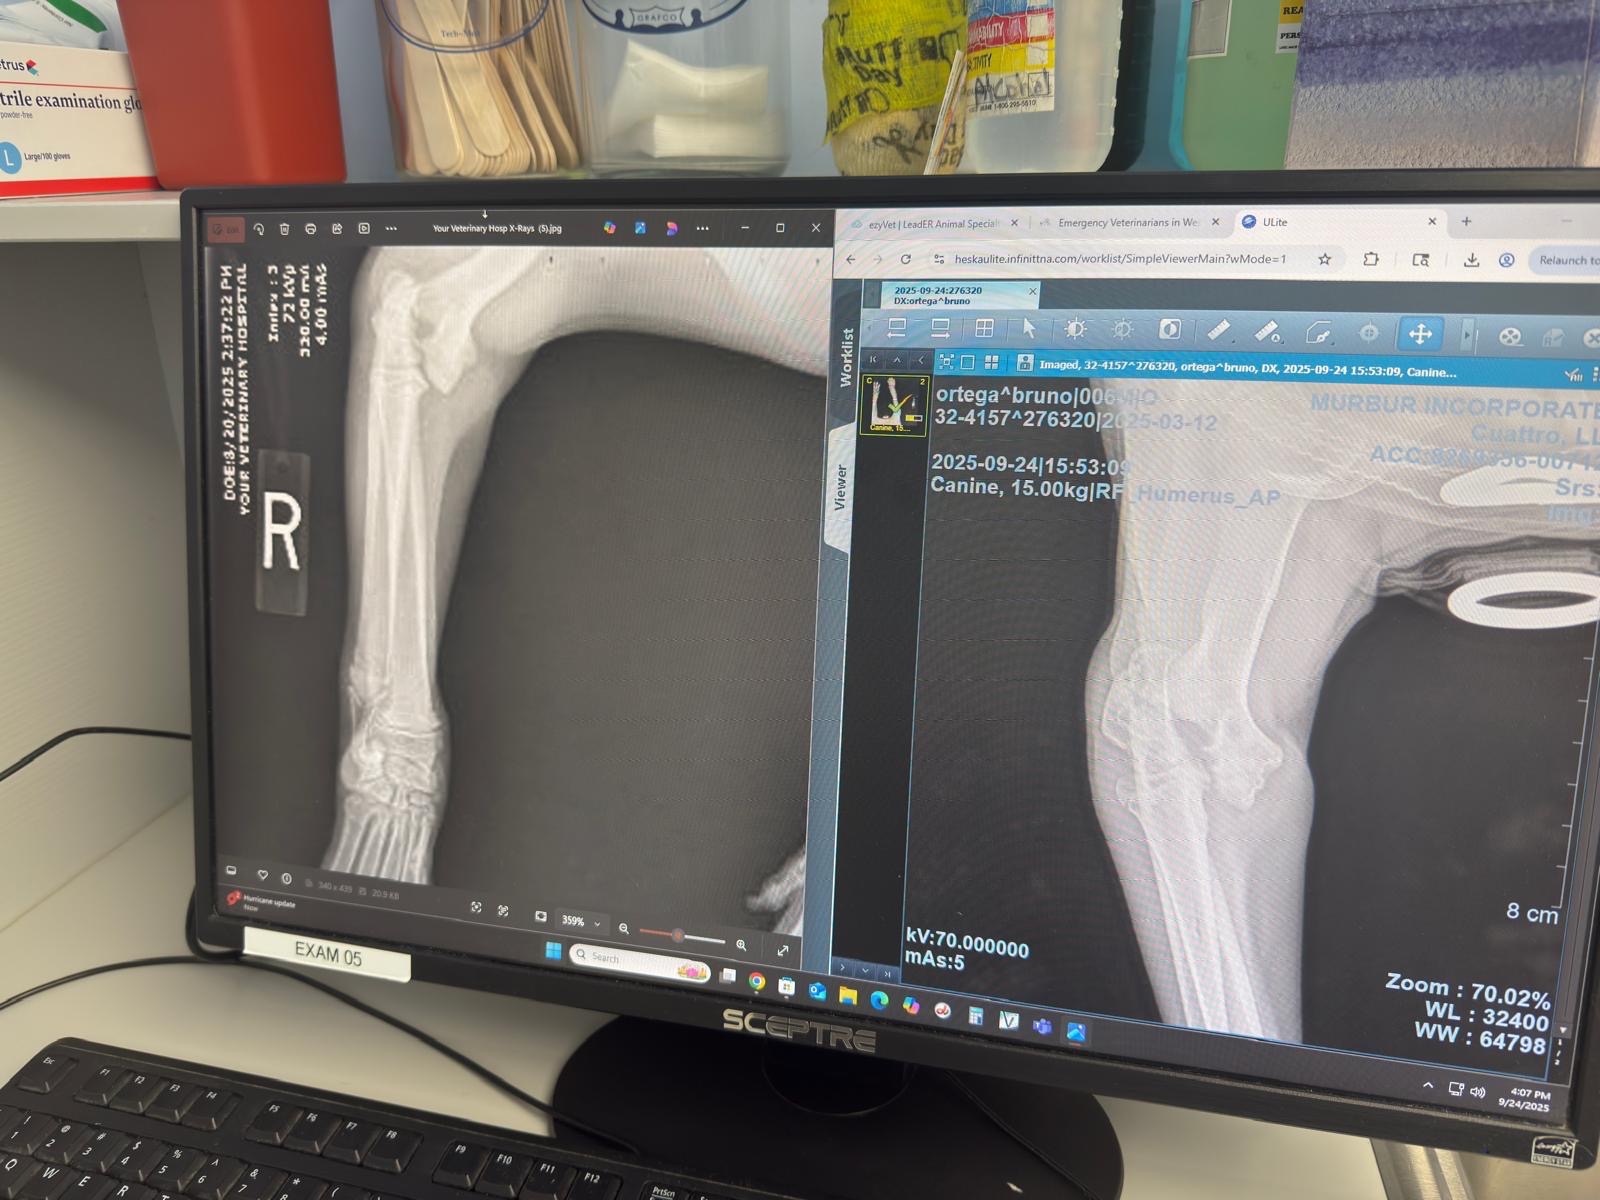

Our baby Bruno fractured his leg and is in need of surgery asap. Unfortunately if does not have this surgery we will have to amputate his leg in a month. We currently have no funds to do the surgery since we’ve already accumulated several vet bills since the accident. Any amount of donation goes a long way. Please help us get our baby the surgery he needs. Thank you in advance. God Bless

Nuestro bebé Bruno se fracturó la pierna y necesita cirugía lo antes posible. Lamentablemente, si no se opera, tendremos que amputarle la pierna en un mes. Actualmente no contamos con fondos para realizar la cirugía, ya que hemos acumulado varias facturas veterinarias desde el accidente. Cualquier donación es muy valiosa. Por favor, ayúdennos a conseguir la cirugía que nuestro bebé necesita. Gracias de antemano, Dios los bendiga.